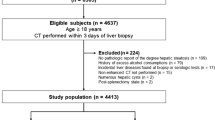

Living liver donor candidates who underwent abdominal CT and liver biopsy for pre-donation workup between January 2013 and December 2014 were consecutively identified. Inclusion criteria were: (a) subjects with abdominal CT scans; (b) at least two biopsy specimens; and (c) less than 3 months interval between CT and liver biopsy. Among 758 subjects initially recruited, 41 were excluded (24 with biopsy–CT interval of > 3 months; 17 without unenhanced CT images). Subjects who fulfilled the inclusion criteria were eligible, regardless of the degree of their HS. The remaining 717 subjects [480 men; median age, 28 years; interquartile range (IQR), 22–35] were finally included. This retrospective study was approved by the institutional review board of our institution and the requirement for written informed consent was waived.

The characteristics of the 717 subjects are summarized in Table 1. There were 457 (63.7%) subjects with TS < 5%, 239 (33.3%) with TS 5–30%, 17 (2.4%) with TS 30–60%, and four (0.6%) with TS ≥ 60%. For MaS, 634 subjects (88.4%) had MaS < 10%, 66 (9.2%) had MaS 10–30%, 30%, and 17 (2.4%) had MaS ≥ 30%. The median differences in body weight and body mass index between the time of liver biopsy and CT examination were 0.9 kg (IQR, 0.4–1.9 kg) and 0.3 kg/m2 (IQR, 0.1–0.6 kg/m2), respectively, in all study subjects, and 2.1 kg (0.8–5.2 kg) and 0.7 kg/m2 (IQR, 0.3–1.7 kg/m2) in the 69 subjects with a biopsy–CT interval of more than one month.